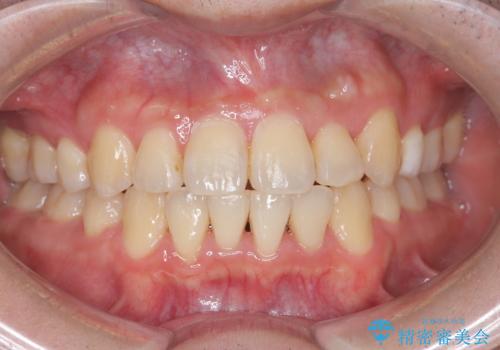

【重度叢生ワイヤー矯正】きれいな歯並びにしたい

- きれいな歯並びにしたいとの希望を持って来院された患者様です。

骨格的3級傾向もあり、咬合関係を仕上げるのに時間がかかりましたが、患者様には大変満足していただけました。

難しいケースでしたが、矯正用アンカースクリューを用いながら、臼歯関係もきれいに仕上げることができました。